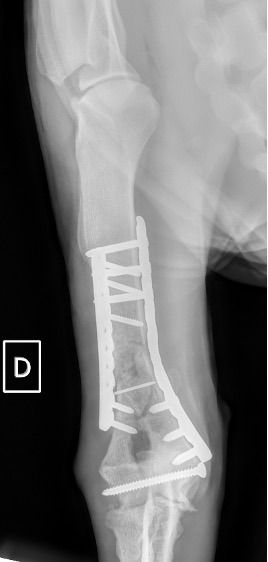

Notre préférence va vers le placement de deux plaques humérales : une médiale de la plus grande taille possible et l’autre latérale, généralement d’une taille inférieure à la première. Dans l’exemple 1 (chat européen), une plaque de 2 mm est utilisée médialement et une plaque de 1,5 mm latéralement. Dans l’exemple 2 (chien Malinois), une plaque de 3,5 mm est utilisée médialement et une plaque de 2,7 mm latéralement.

Figure 2 : Post-Op Immédiat

Exemple 2 :

Figure 5 : Post-Op Immédiat